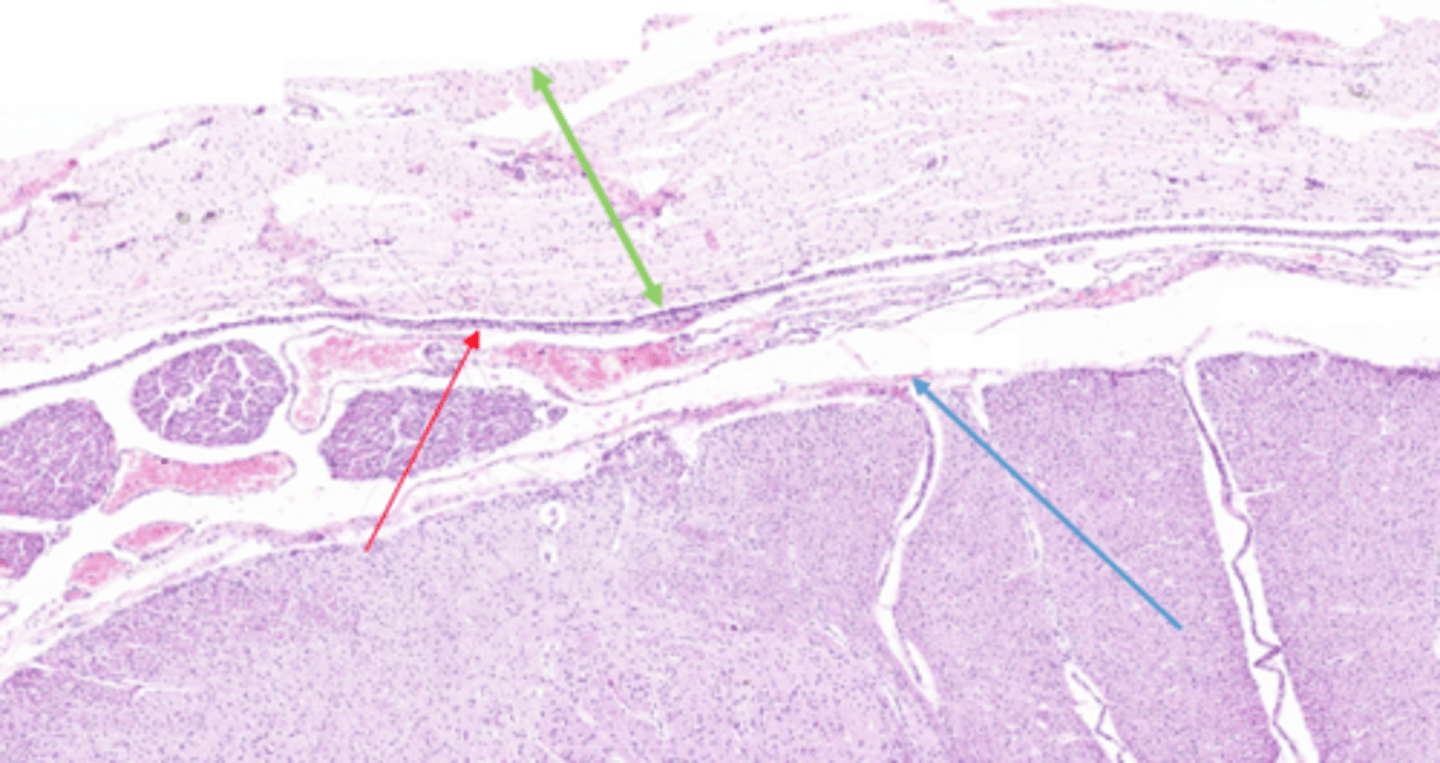

Dorsal Root Ganglion

8

Unipolar Neurons

What neurons are found in 8?

Pia Mater

Blue Arrow

Dura Mater